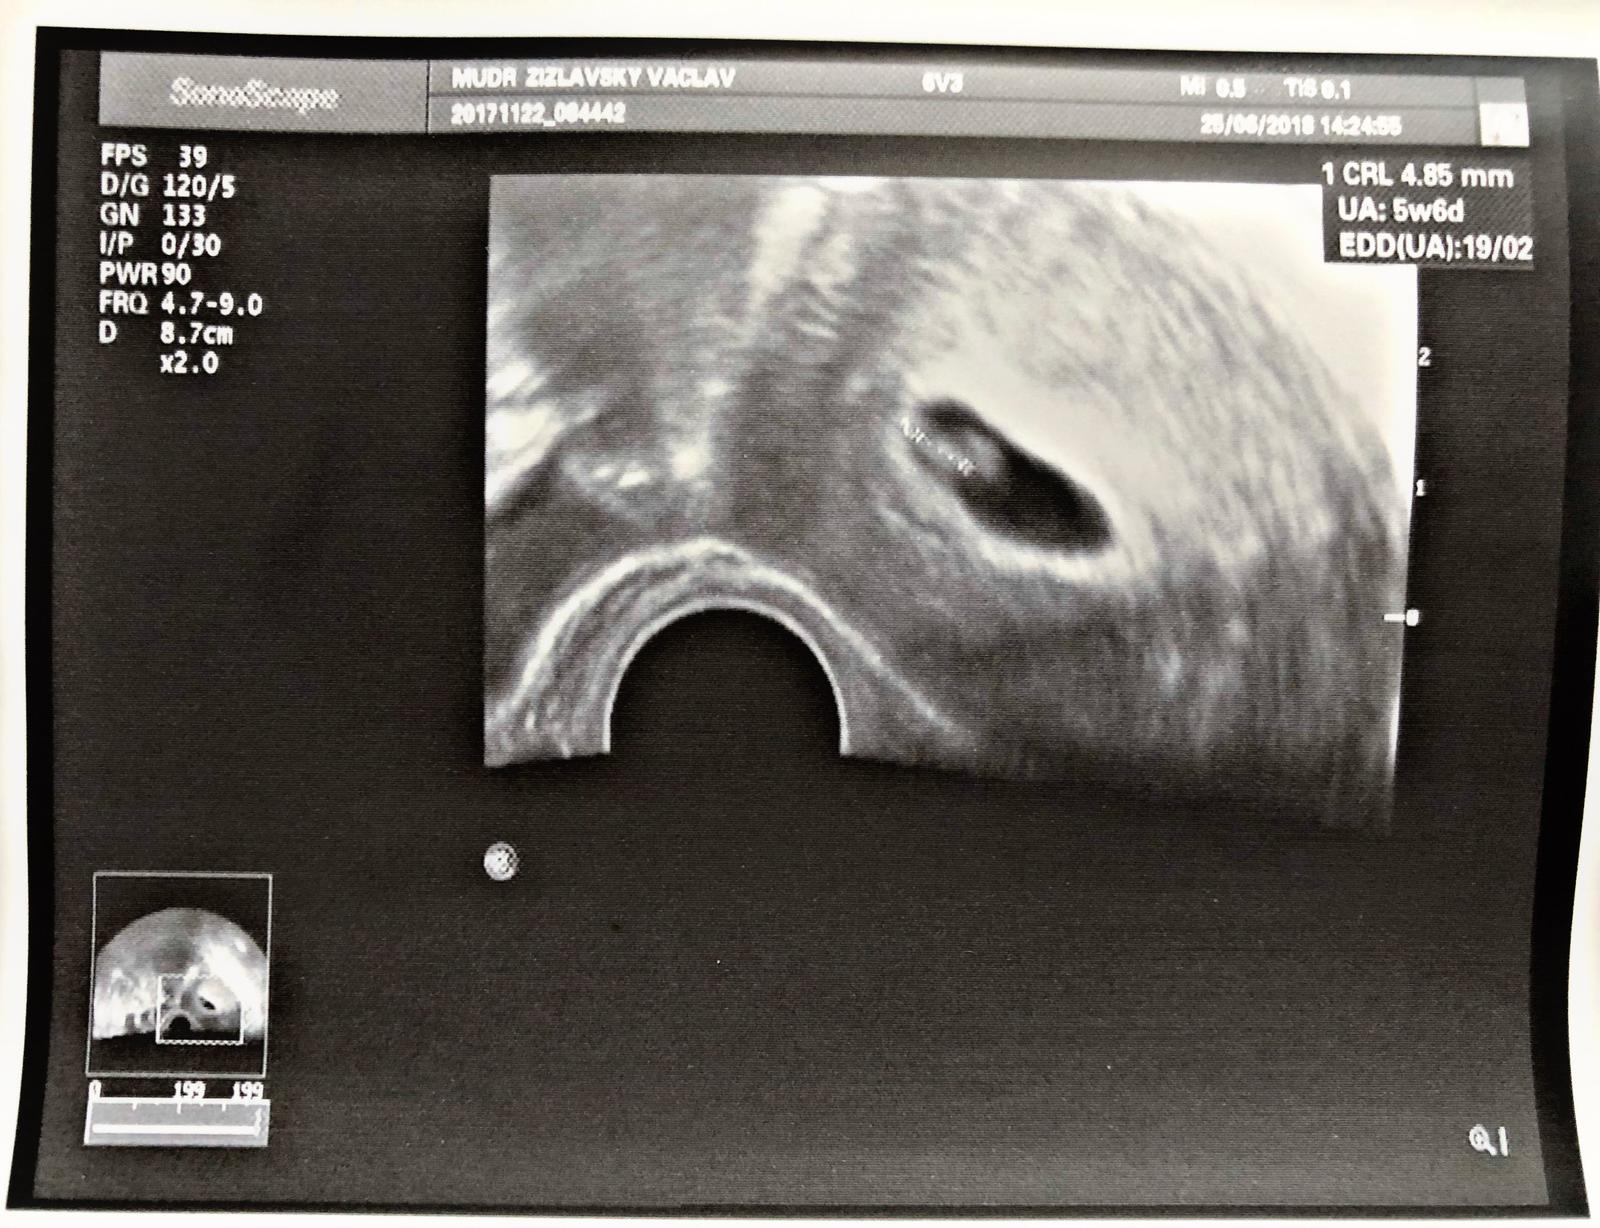

Termín porodu únor 2019